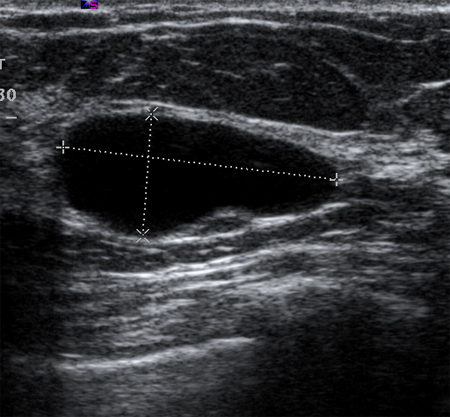

A ultrassonografia pode identificar estruturas císticas simples ou complexas.[51] Cistos simples são lesões preenchidas por fluidos que têm apresentação lisa, arredondada, bem-demarcada e anecoica. Se eles não tiverem septações ou detritos celulares internos, eles podem ser simplesmente acompanhados. A ultrassonografia não é capaz de detectar microcalcificações na mama.[Figure caption and citation for the preceding image starts]: Imagem ultrassonográfica de um cisto simplesCortesia do Dr. Lane Roland, Universidade de Louisville; usado com permissão [Citation ends].

A aspiração guiada por ultrassonografia pode ser realizada. O líquido do cisto aspirado não deve ser enviado para citologia porque, com a exceção de líquido cístico hemorrágico, não se costumam identificar células malignas.[73]